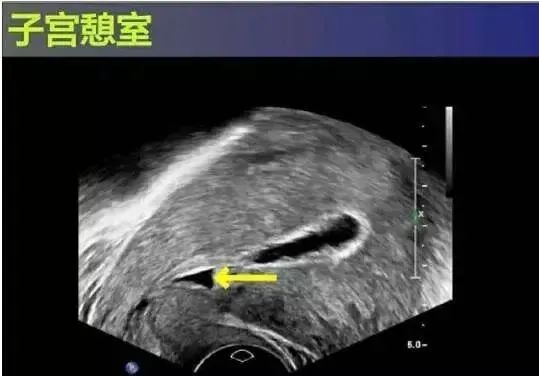

子宫是女性活力的源泉,青春和魅力的守护神。但同时,子宫也是一个脆弱而敏感的器官,很多因素都可能导致子宫出血,影响子宫健康。国内近年来随着剖宫产率的增高,剖宫产术后月经异常患者增加,并且诊断为子宫切口憩室的病例增多,子宫挨了刀子,导致宫中格局改变,多了一个空间,形成了憩室。

因为是多出来的空间,所以宫壁相对就薄很多,憩室本就是一个凹陷的空间,该凹陷下端瘢痕由于活瓣作用而阻碍了经血的引流,经血积聚于凹陷内,导致经期延长、不规则阴道出血,甚至不孕、痛经等症状,少数再次妊娠患者,若孕囊着床在此部位可以形成疤痕妊娠,极为凶险。